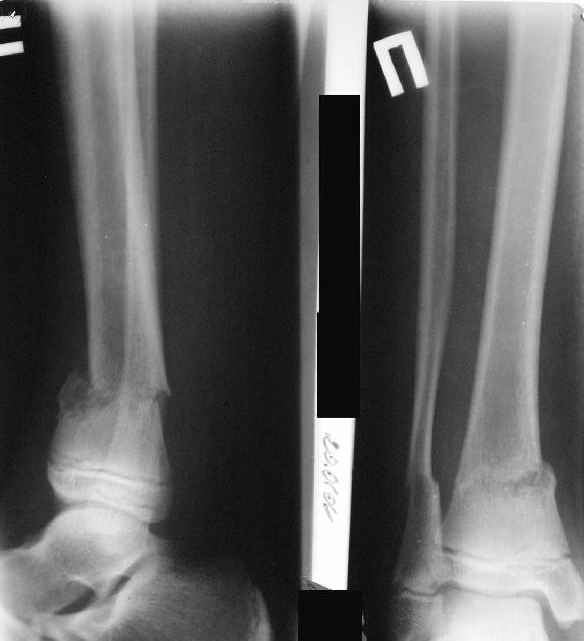

Деформация появилась и наростала во времени при фиксации в гипсовых повязках.

AVM> А каково у него укорочение голени?

В пределах 2 см.

Не катастрофа. Рост продолжается, будем следить в динамике.

Промежуточный